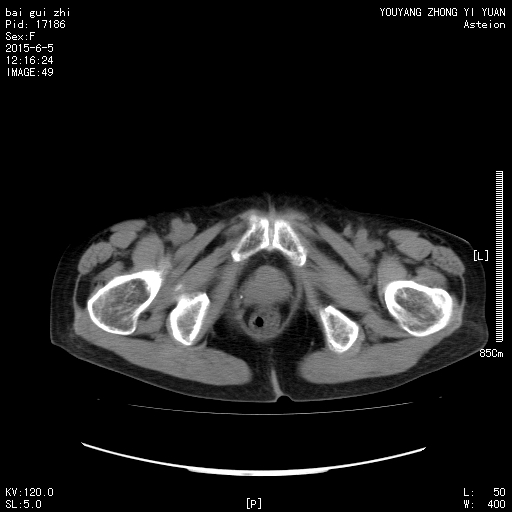

CT50572:急!请老师们看一下阑尾。

患者女性,74岁,右下腹痛5天。临床怀疑化脓性阑尾炎。

盲肠肠壁增厚,周围脂肪间隙浑浊,考虑炎症存在。

盲肠肠壁增厚,其它未见异常。

不典型

腹膜后感染性病变,结合临床

不典型,即使是也没见化脓改变。